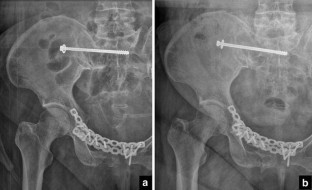

Fig. 4